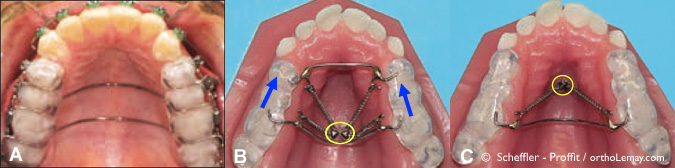

Fig (4) – Après 10 mois de traitement, les dents sont alignées (correction des rotations et du chevauchement dentaire) et les mini-vis d’ancrage furent posées. (A) Appareils orthodontiques en bouche avec les mini-vis d’ancrage indiquées par les cercles jaunes. Des ressorts de traction sont attachées entre les vis et des crochets sur l’appareil d’ancrage collé aux dents (visible en (B)). L’appareil d’ancrage et les mini-vis d’ancrage peuvent être utilisées sans la pose de brackets. Lors de la pose de l’appareil d’ancrage, la béance antérieure semblera augmenter à cause de l’épaisseur de plastique (acrylique) entre les dents mais ceci se corrigera à mesure que l’ingression des dents postérieures se produira et la béance antérieure fermera.